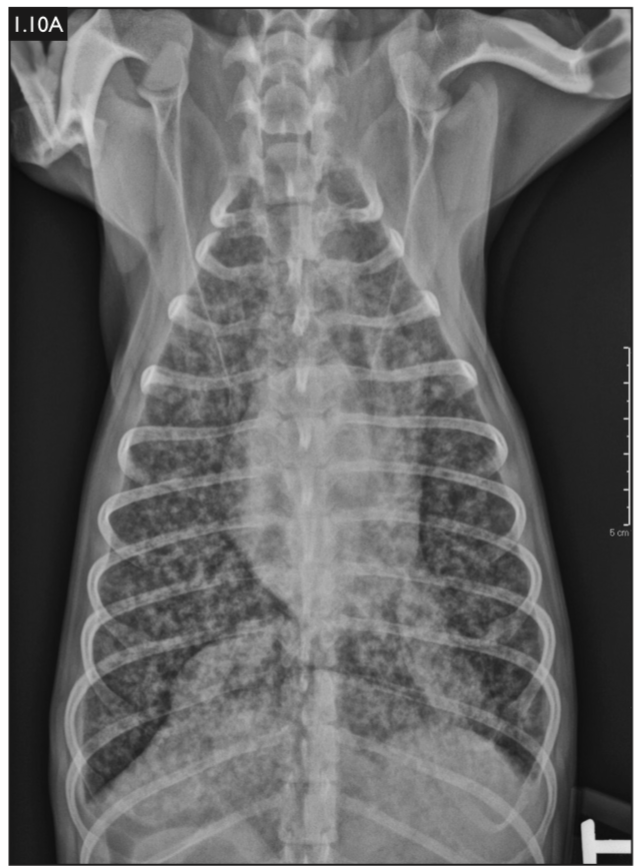

Chest x-ray showing ribs, spine, and lungs.